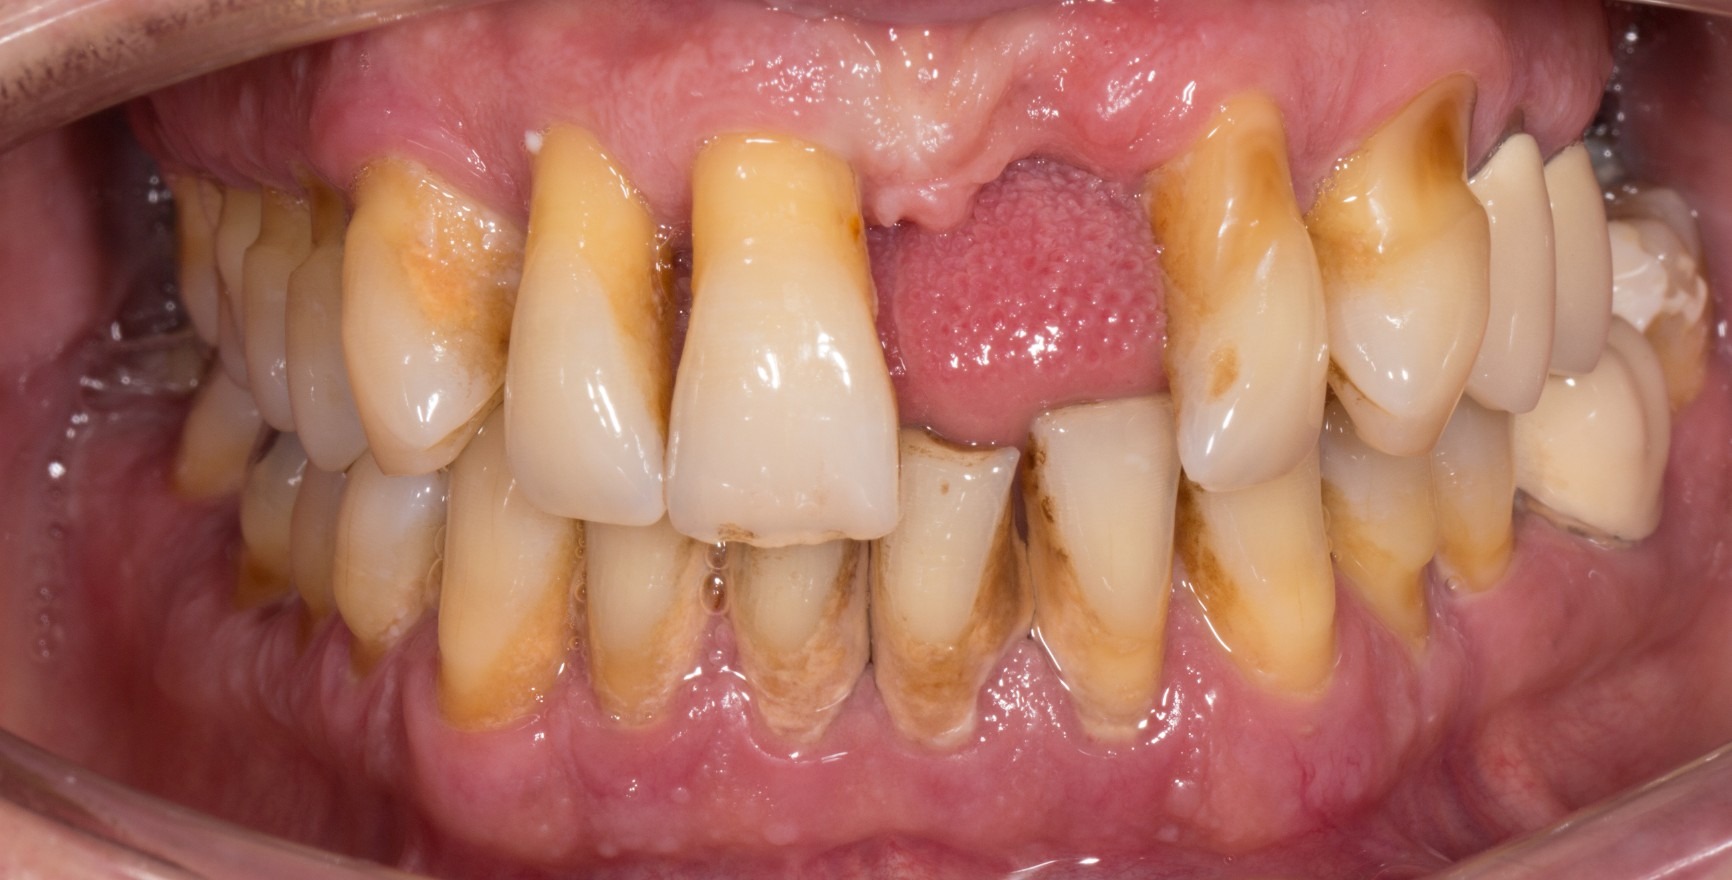

Die im Juni 2018 vorgestellte neue Klassifikation der parodontalen Erkrankungen enthält erstmalig eine Definition des Begriffs der klinischen parodontalen Gesundheit (Lang & Bartold, 2018). Im gingivalen Sulkus ist auch unter optimalen Hygienebedingungen eine geringe Menge eines bakteriellen Biofilmes vorhanden, eine absolute Keimfreiheit ist unter klinischen Bedingungen nicht denkbar. Als Reaktion findet sich histologisch ein begrenztes subepitheliales Infiltrat aus neutrophilen Granulozyten (PMN). Solange jedoch die Homöostase zwischen Biofilm und einem geringen PMN-Infiltrat erhalten bleibt, wird dieser Zustand als Ausdruck einer immunologischen Kontrolle und damit als physiologischer und nicht als pathologischer (Entzündungs-) Prozess angesehen (Brecx et al., 1987a+b). Ob der Zustand klinischer parodontaler Gesundheit bestehen bleibt, hängt von der mikrobiologischen Belastung und Wirtsfaktoren ab. Diese können lokal zu einer vermehrten Biofilmakkumulation führen wie z.B. unzulängliche zahnärztliche Restaurationen oder ungünstige Zahnstellungen oder die Immunantwort beeinflussen wie etwa systemische Erkrankungen.

Unterschieden wird ein Zustand klinischer parodontaler Gesundheit am intakten Parodontium von dem am reduzierten Parodontium, bei dem bereits ein klinischer Attachmentverlust eingetreten ist. Dieser Attachmentverlust kann entstanden sein:

entzündungsbedingt im Verlauf einer Parodontitis. Klinische parodontale Gesundheit beschreibt dann den stabilen Zustand nach einer erfolgreich abgeschlossenen parodontalen Therapie.

in Folge von Rezessionen

iatrogen, z.B. durch chirurgische Kronenverlängerung (Chapple et al., 2018)

Klinisches Kriterium ist immer das Ausbleiben einer Blutung nach vorsichtiger Sondierung (Bleeding on Probing = BoP). Man differenziert zwischen einer stellen- bzw. zahnspezifischen Diagnose mit negativem BoP-Befund an der entsprechenden Messstelle bzw. einem Zahn und einer auf den Patienten bezogenen Diagnose, bei der ein Schwellenwert von einem BoP ≤ 10 % noch die Kriterien der klinischen parodontalen Gesundheit erfüllt. Die Sondierungstiefen dürfen maximal drei Millimeter betragen, bei reduziertem Parodontium nach parodontaler Therapie wird noch bei einem Grenzwert von vier Millimetern ein stabiler Zustand angenommen (Matuliene et al., 2008).